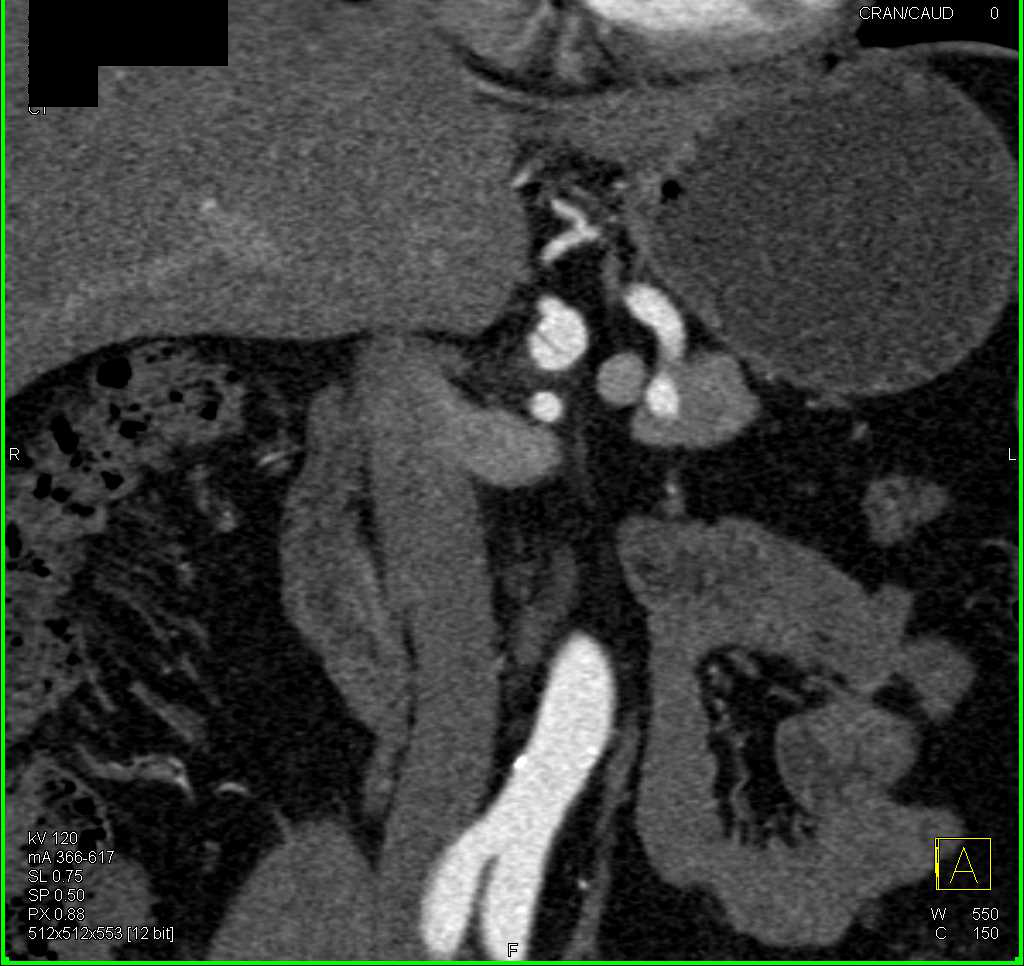

Atherosclerotic Disease Aorta and Mesenteric Vessels